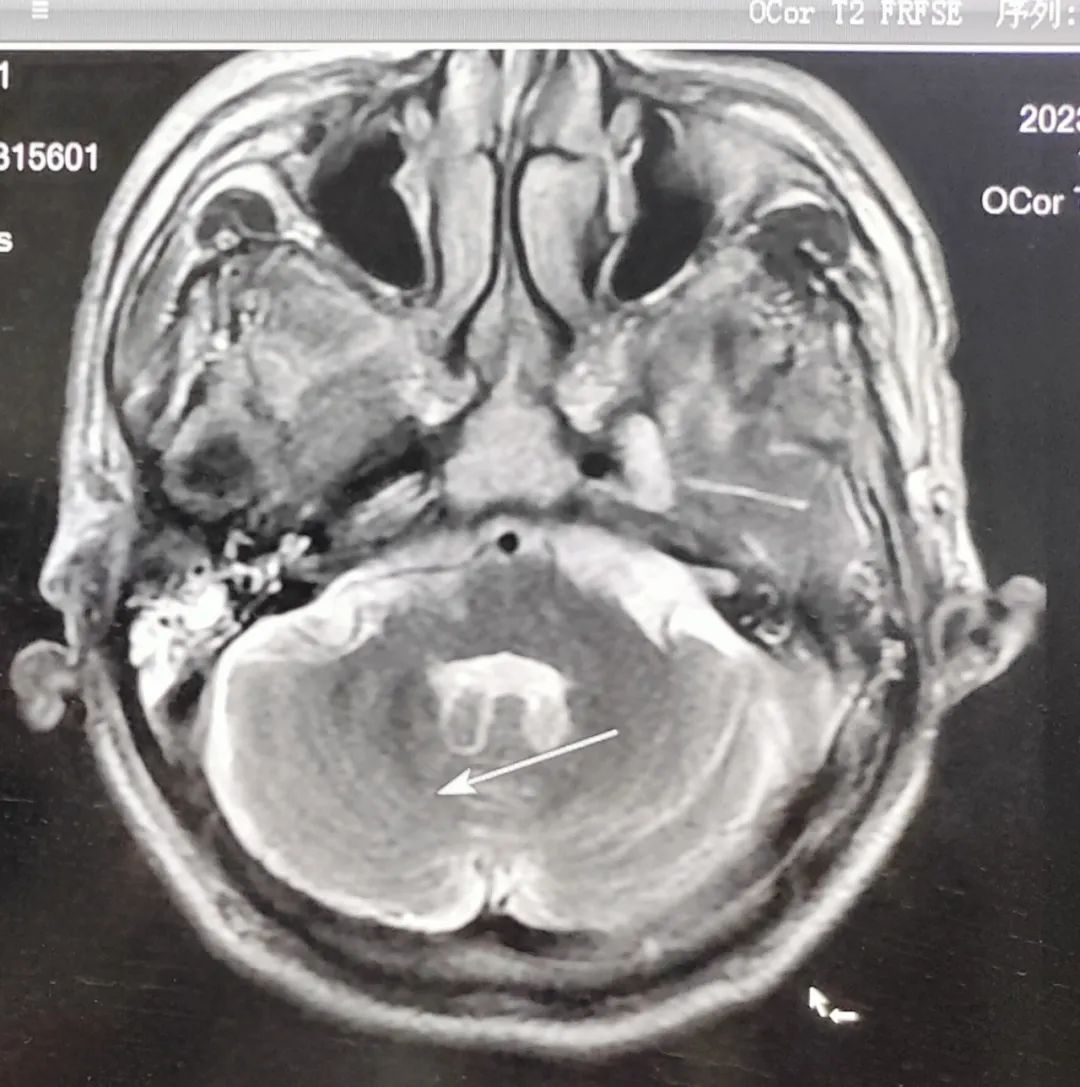

患者林女士,2023年7月确诊为肺癌晚期。由于病灶压迫肺门及大血管,无法进行手术治疗,化疗后出现耐药,于10月份发现脑部转移,对于病情快速恶化的林女士犹如雪上加霜。我院肿瘤放疗科陈春荣医生结合患者病情,采取个体化精准放疗及综合治疗。经过两月余治疗后,患者病情得到了有效控制,对生活再次充满信心。

头部调强放疗前后对比图